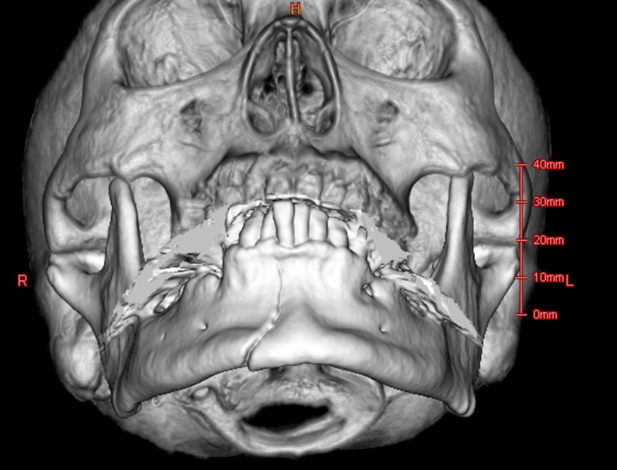

交通事故、転倒、スポーツ外傷などによる顎顔面外傷に対し、迅速かつ適切な診断・治療を提供します。顎骨骨折、顔面骨折、軟部組織損傷など、様々な外傷に対応し、救急科や他診療科とも連携して早期治療に努めます。

下顎骨骨折

頬骨上顎骨複合骨折